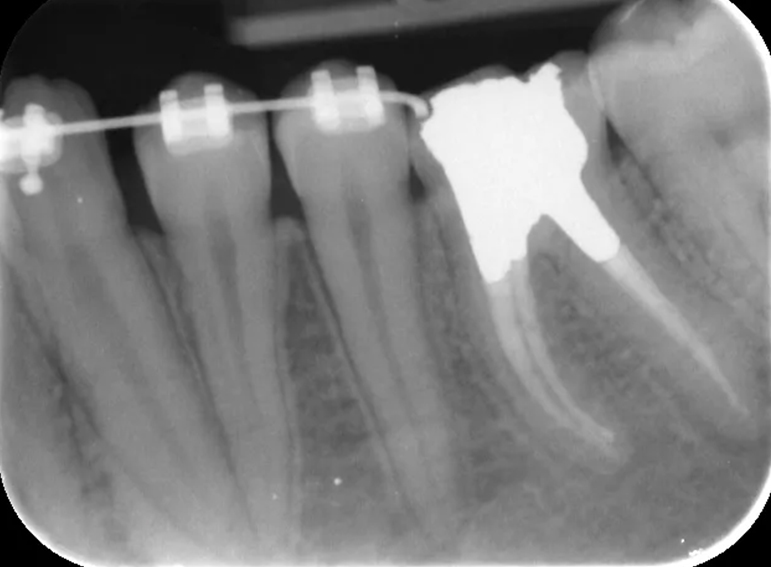

Surgical extrusion, root canal and apexification treatment of UL1 and composite build ups of UR1 and UL1 following…